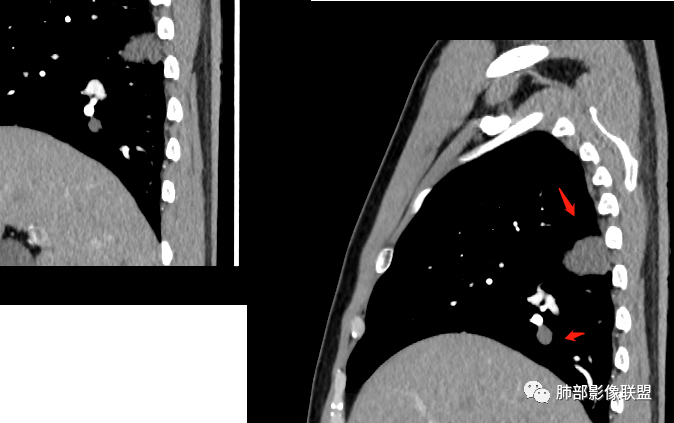

中年男性,体检发现占位。右肺下叶背段胸膜下肿块,周围晕征,有小分叶,与支气管、肺内血管关系不清,形似山丘,重建可见肿块呈D字形凸向肺部。似跨斜裂,似有小凸起与肋下缘相连,增强似有轻微均匀强化。右肺下叶外基底段小结节,位于血管周围,部分边缘平直,轻微均匀强化。考虑二元:一、右下叶背段肿块为肺外病变,神经鞘瘤?SFT?鉴别小细胞癌、隐球菌病;二、右下叶外基底段结节考虑为良性结节、炎性肉芽肿?

2.右肺下叶背段胸膜下块影,边界清楚光整,上下极见磨玻璃晕,未见明显分叶毛刺和棘状突起,未见胸膜凹陷或胸壁侵入。密度均匀,轻度不均匀强化。未见支气管进入。

4.右肺下叶基底段支气管血管束旁小结节影,边界清楚,强化不明显。注意,这结节在“遥远的”基底段。

3、卫星灶与“蘑菇兄弟”:诊断隐球菌时,建议找卫星灶,卫星灶可以在遥远的地方。可以是遥远地方的微小结节——“小蘑菇兄弟”。有些远处的卫星灶,通常是不规则饱满实性的,晕征不明显。隐球菌的卫星灶非常“隐”,但发现率高达60%多,诊断价值高。

4、卫星灶距离远的原因:隐球菌卫星灶常很远,推测:一次空气来源隐球菌感染进入双肺多处,部分定居繁殖;距离近的隐球菌“蘑菇兄弟”常常是二次感染。